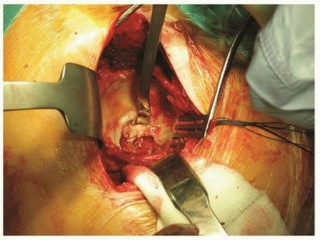

INDICATIONS Approaching the hip joint from a posterior direction was originally described by the German surge…